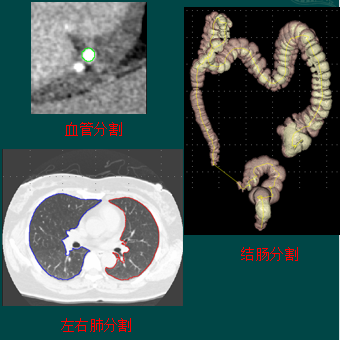

2、分割

根据目标物体特征,把图像划分为若干个互不相交的区域,使得这些特征在同一区域内,表现为一致性或相似性,在不同区域表现明显不同。

可辅助医生进行诊断和制定对病人的治疗方案;

用于医学图像的分析,如三维重建;

用于计算机引导于术,如外科手术的制定,病理的研究;

心脏组织自动分割

-

血管树解析

结肠

计算机断层扫描结肠成像(Computed Tomography colonography, CTC)是一种微创技术,是一种替代光学结肠镜检查结直肠息肉的方法 。

2D横截面CT图像或者结肠内空气3D表面的形式呈现。

结肠CAD(虚拟内窥)

虚拟内窥功能包括沿着中心线方向的虚拟自动漫游,以及手动漫游。

结肠CAD(虚拟切开)

结肠虚拟切开包括“立方体虚拟切开”来显示360 度的三维全景和切开在一个平面上显示的整个结肠二维全景。